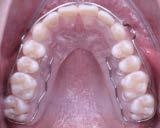

Figura 18. Vista oclusal y frente de los retenedores circunferenciales.

Introducción: La ortopedia funcional de los maxilares, a través de estímulos del crecimiento en la dirección correcta, nos beneficia para corregir maloclusiones en un estadio temprano con tratamientos sencillos, previniendo alternativas ortodóncicas y quirúrgicas futuras. Objetivo: reportar tratamiento ortopédico clase II división 2, con mordida profunda, paciente en crecimiento. Metodología: Niño de 10 años empleando aparatología ortopédica de Simoes Network SN1 y recambio de Pistas Planas PIPS. Resultados: con el uso del SN1 con equiplan corregimos la mordida profunda en un periodo de 12 meses con su uso continuo y con el PIPS, durante 7 meses dando la estabilidad oclusal. Conclusión: la ortopedia funcional de los maxilares, debe de ser el tratamiento de elección en dentición primaria y mixta. Aunque nuestro paciente presentó una dentición mixta tardía obtuvimos una remodelación y redirección en el crecimiento óseo. Ayudando al paciente en su desarrollo físico y psicosocial. Dependemos al 100% de la cooperación del paciente por lo cual es indispensable el poder estimularlos y alentarlos en el uso correcto de los aparatos.

Figura 1. Fotografías intraorales y lateral de cráneo. A. Vista lateral (VL) derecha en oclusión. B. Vista frontal (VF) en oclusión. C. VL izquierda en oclusión. D. Radiografía lateral de cráneo.

Figura 2. Fotografías oclusales y ortopantomografía. A. Vista de la arcada superior. B. Vista de la arcada inferior. C. Ortopantomografía.

Reporte de caso clínico

Paciente masculino de 10 años, se presenta a la consulta en la clínica Gnathos, la mamá reporta desagrado en la estética dental y facial del paciente. En la exploración clínica se observa mordida profunda, amplio número de piezas dentales con caries, fracturas dentales, mala higiene y encías inflamadas. presenta clase II división 2, se le indicaron estudios complementarios para diagnóstico asertivo, modelos de estudio,

Tratamiento de mordida profunda

radiografía panorámica y lateral de cráneo, fotografía intraoral y extraoral, historia clínica y consentimiento informado.

Metodología

Después de haber realizado el diagnóstico y plan de tratamiento, se remitió a extracción de restos

Figura 3. Primer aparto SN1 con almohadillas vestibulares. A. VF con aparato, B. VL derecha C. VL izquierda. D. SN1, vista oclusal (VO). Después de 7 meses del tratamiento se observa los avances obtenidos por el aparato y los ajustes del mismo los cuales observamos en las figuras: E. VO del SN1 7mm de crecimiento transversal, F. VF con aparato, 3G. VL derecha, H. VL izquierda.

Investigación clínica

Figura 4. Segundo Aparato SN1. A. VF con aparato, B. VL derecha, C. VL izquierda, 3D. SN1, VO. Después de 5 meses del tratamiento se observa los avances obtenidos por el aparato y los ajustes del mismo los cuales observamos en la imagen, E. VO del SN1 5 mm de crecimiento transversal, F. VF con aparato, G. VL derecha, H. VL izquierda.

Figura 5. Tercer aparato PIPS A. VF con aparato, B. VL derecha, C. VL izquierda, D. PIPS VO. Después de 7 meses del tratamiento se observa los avances obtenidos por el aparato y los ajustes del mismo los cuales observamos en la imagen, E. VO del PIPS sin los mantenedores de espacio, 5. VF con aparato, 5G. VL derecha, 5H. VL izquierda.

radiculares de O.D. 73 y 83 y rehabilitación oral completa de O.D. 54, 63,65 y 75. Se procedió a colocar aparatos ortopédicos para corrección de la maloclusión en enero del 2022.

El tratamiento inicio con AOF, SN1 con Equiplan adicionando almohadillas vestibulares en el maxilar para despresurizar la acción de la musculatura labial. La indicación de uso fue utilizarlo de forma continua solo retirándose para comer e higienizar, activar del tornillo tanto superior como inferior una vez a la semana, y se realizaron revisiones mensuales en la clínica para valorar avances, llevar

a cabo activaciones, ajustes del aparato e indicaciones. Como se observa en la Figura 3.

Al haber obtenido los avances programados en la corrección de la sobremordida vertical con esté AOF, se decide cambiar a un nuevo SN1, con equiplan sin almohadillas y con arco vestibular esto para continuar regularizando el plano de oclusión en el paciente, y fue utilizado por 5 meses de forma continua. Se mantuvieron las mismas indicaciones de uso, que en el aparato anterior. Como podemos observar en la Figura 4

El AOF Sn1 logró el avance mandibular, expansión programada, armonización de arcadas y regularización de la curva de Spee, entonces se determina cambiar dicho aparato por unas PIPS, clase I para mantener el espacio que corresponde a los O.D. 35 y 45, ya que fueron indicadas para extracción los O.D. 75 y 85, esperando la erupción de premolares para terminar el anclaje. Las indicaciones para el paciente fueron uso continuo de las PIPS por 3 meses, solo retirándose para comer e higienizar, revisiones mensuales en la clínica para activación y desgastes de los mantenedores de espacio, vigilando la erupción de los premolares. Posteriormente se indicó su uso nocturno por 4 meses más para mantener estabilidad de los resultados obtenidos.

Después de 18 meses de tratamiento con ortopedia funcional de los maxilares, podemos hacer una comparativa de los resultados obtenidos.

Figura 6. Fotos intraorales antes y después del tratamiento. A. VF B. VL derecha, C. VL izquierda, después de 18 meses de tratamiento D. VF, E. VL derecha, F. VL izquierda.